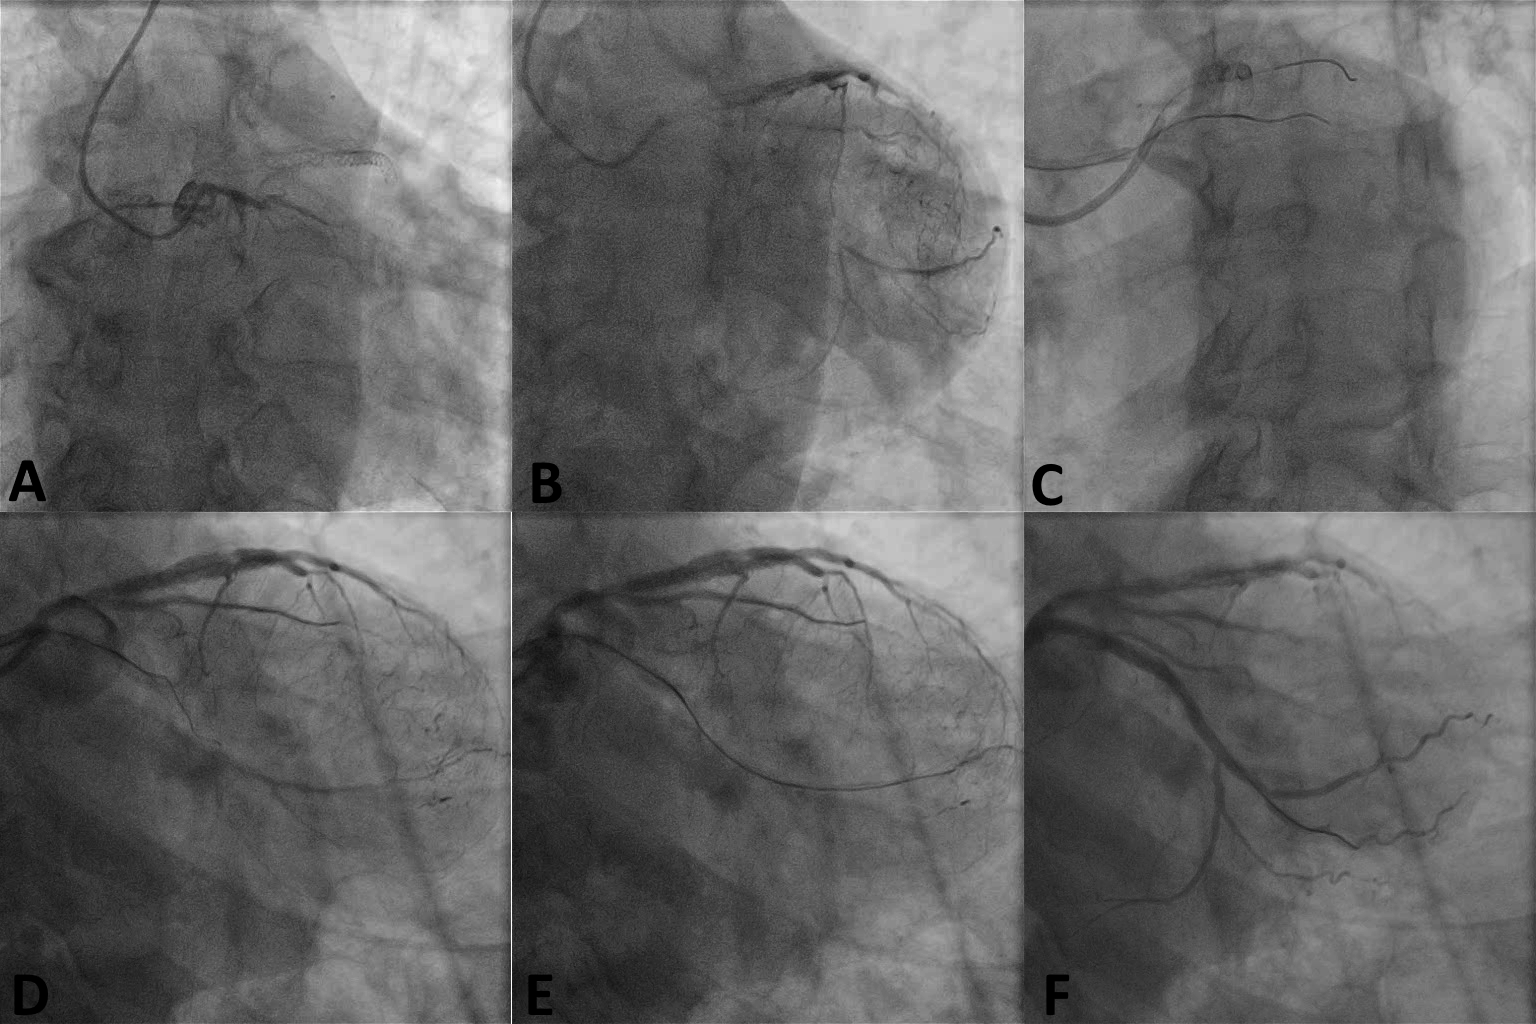

A 60-year-old man was referred for percutaneous coronary intervention of a proximal left circumflex (Cx) chronic total occlusion (CTO) with distal filling via epicardial collaterals from the left anterior descending (LAD) artery. The 30 mm lesion had a clearly defined proximal cap (Figure, A) with a bifurcation present at the distal cap (Figure, B).

An initial antegrade approach with wire escalation was the first option, followed by switching to antegrade dissection re-entry if there was no progress. Due to a short left main, we used 2 guide catheters sub selectively engaging the LAD and the Cx to minimize the risk of causing or extending a Cx dissection during antegrade crossing attempts. Using biradial access, we engaged the Cx with a 7 French (Fr) extra-backup (EBU) 3.0 guide catheter, and the LAD with a 6 Fr EBU 3.5 guide catheter (Figure, C). A Fielder XT guidewire (Asahi Intecc Medical) (Figure, D), supported by a microcatheter, crossed antegrade into the distal true lumen (Figure, E), but the microcatheter could not be advanced through the occlusion. A 1.0 mm x 15 mm Sapphire Pro balloon (OrbusNeich) successfully crossed and dilated the lesion with an excellent final result after stent implantation (Figure, F).